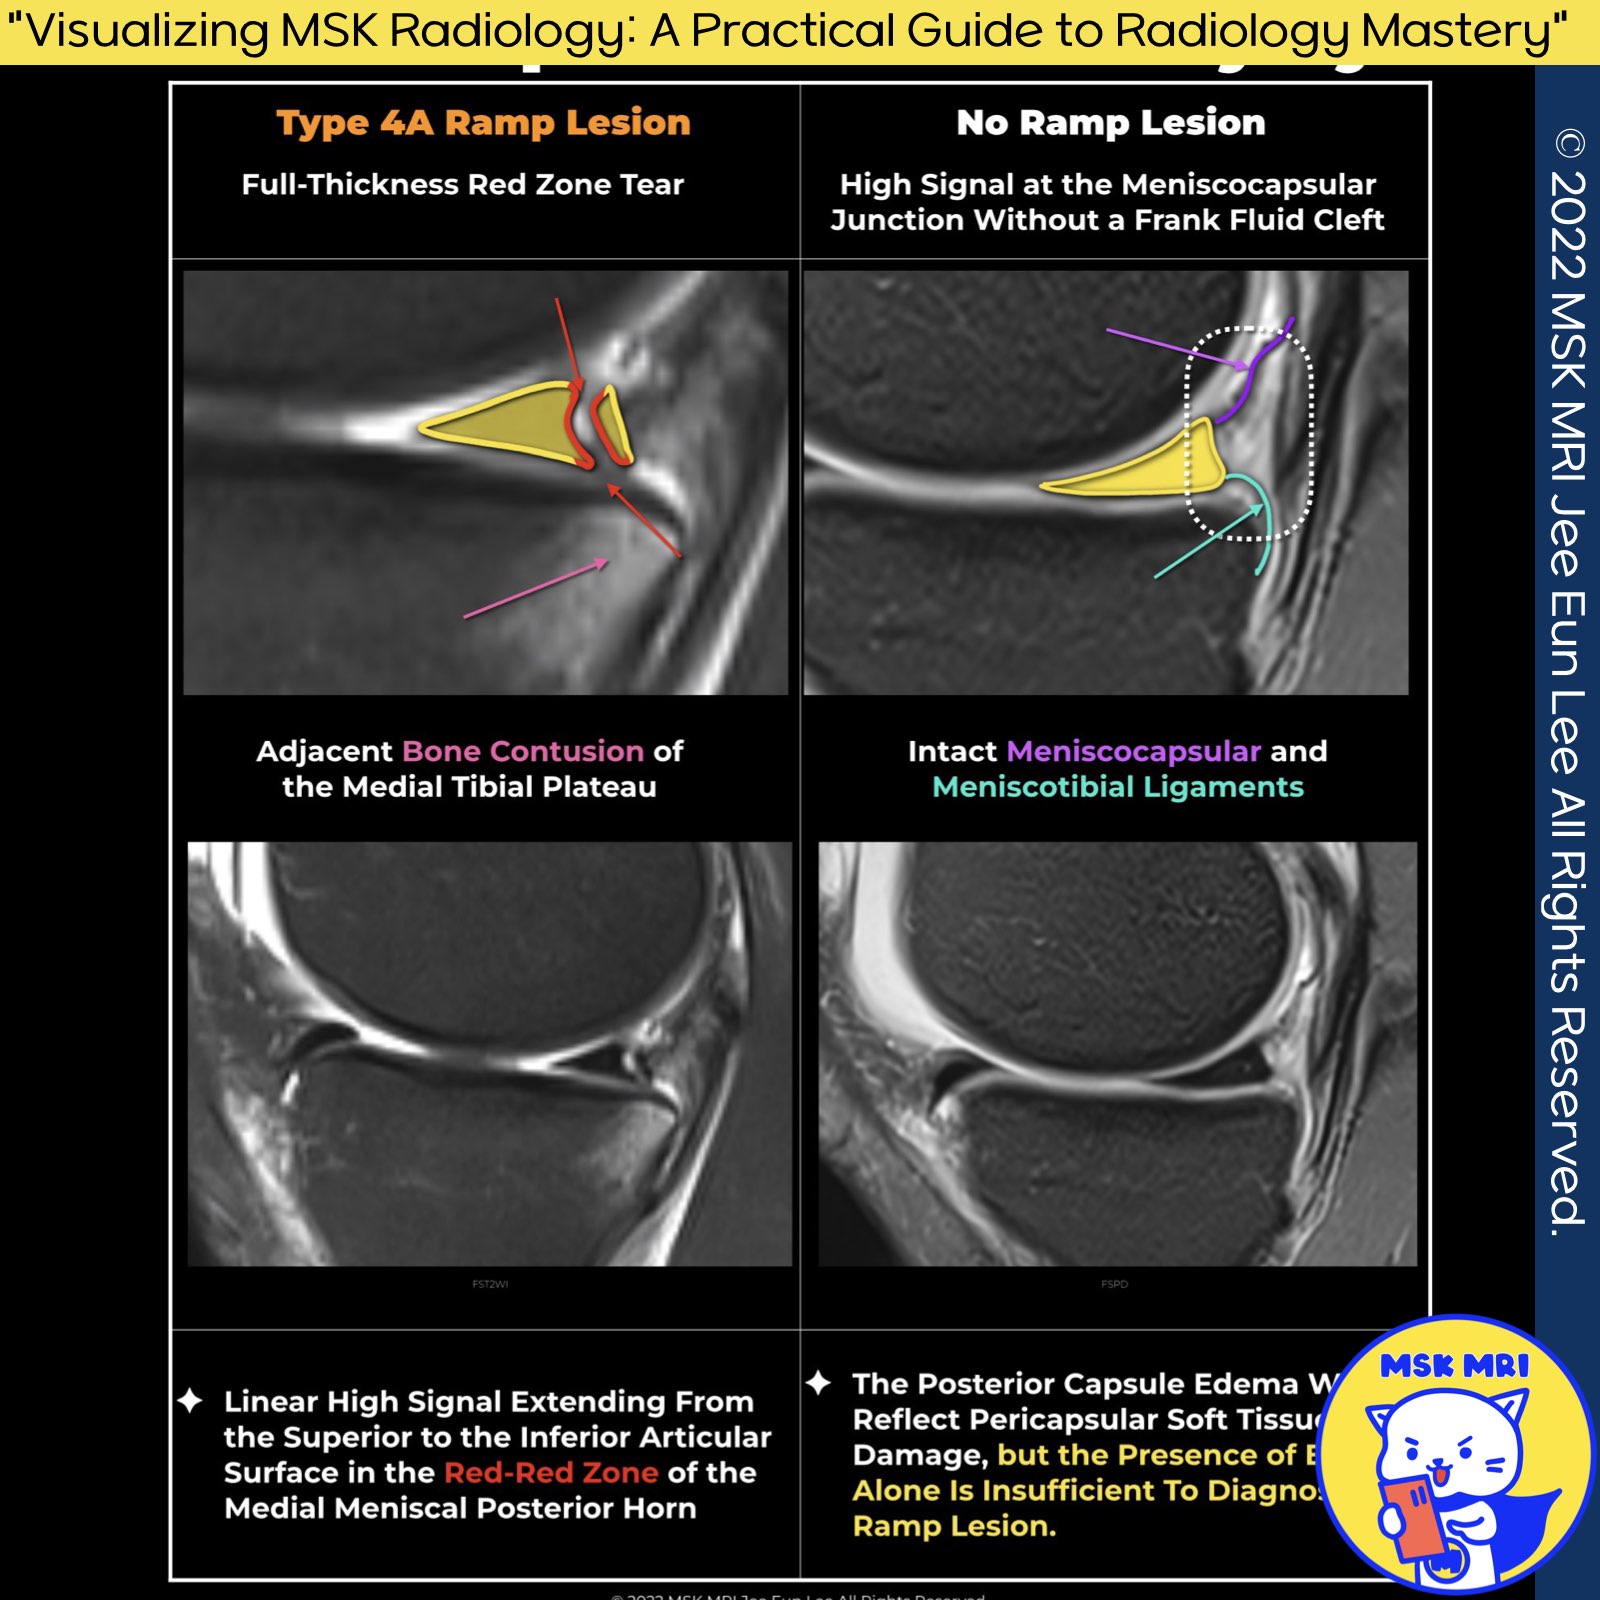

1️⃣ Meniscal Ramp Lesion

- Ramp lesions refer to injuries affecting the posterior horn of the medial meniscus in the setting of ACL tears.

- A high signal at the meniscocapsular junction without a frank fluid cleft indicates a sprain rather than a true separation.

2️⃣ False Positive Ramp Lesions

- Edema affecting the posterior capsule reflects pericapsular soft tissue damage; however, edema alone is insufficient for diagnosing a ramp lesion.

3️⃣ Diagnostic Challenges and Criteria

- No single MRI criterion achieves 100% sensitivity or specificity for diagnosing meniscal ramp lesions.

- The junctional fluid-like signal was found to be highly specific for meniscal ramp lesions, boasting a PPV (Positive Predictive Value) of 92.9%.